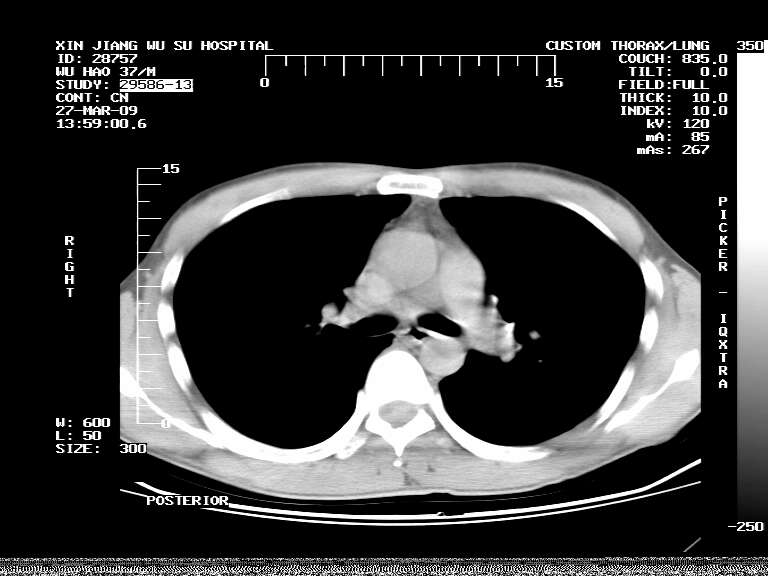

男,37岁,体检胸透发现阴影。

患者体检发现 无症状 左肺下叶占位,边缘模糊,可见血管聚束、分叶、胸膜牵拉,增强呈不均匀性强化。 首先考虑左肺下叶周围型肺癌,建议穿刺活检。

左肺下叶见一结节病变,边缘欠清不光滑,与胸膜粘连且胸膜局限性增厚,注药后呈环形强化,动脉期壁呈明显点环状强化,静脉期壁强化减低,中心密度低无强化,灶周无明显的卫星灶和水肿区(晕征)---考虑周围性肺癌,不除外感染性病变,建议穿刺活检。

左肺下叶软组织病灶,密度较高,内见点状钙化,其周围见子灶,邻近胸膜扁平样增厚.c+病灶强化明显,中心强化弱.诊断:左肺下叶结核瘤.

左肺下叶大片实变影,内靠胸膜见不规则更高密度结节灶,边缘强化,相邻胸膜增厚,胸膜下脂肪线存在。考虑炎症,结核可能。